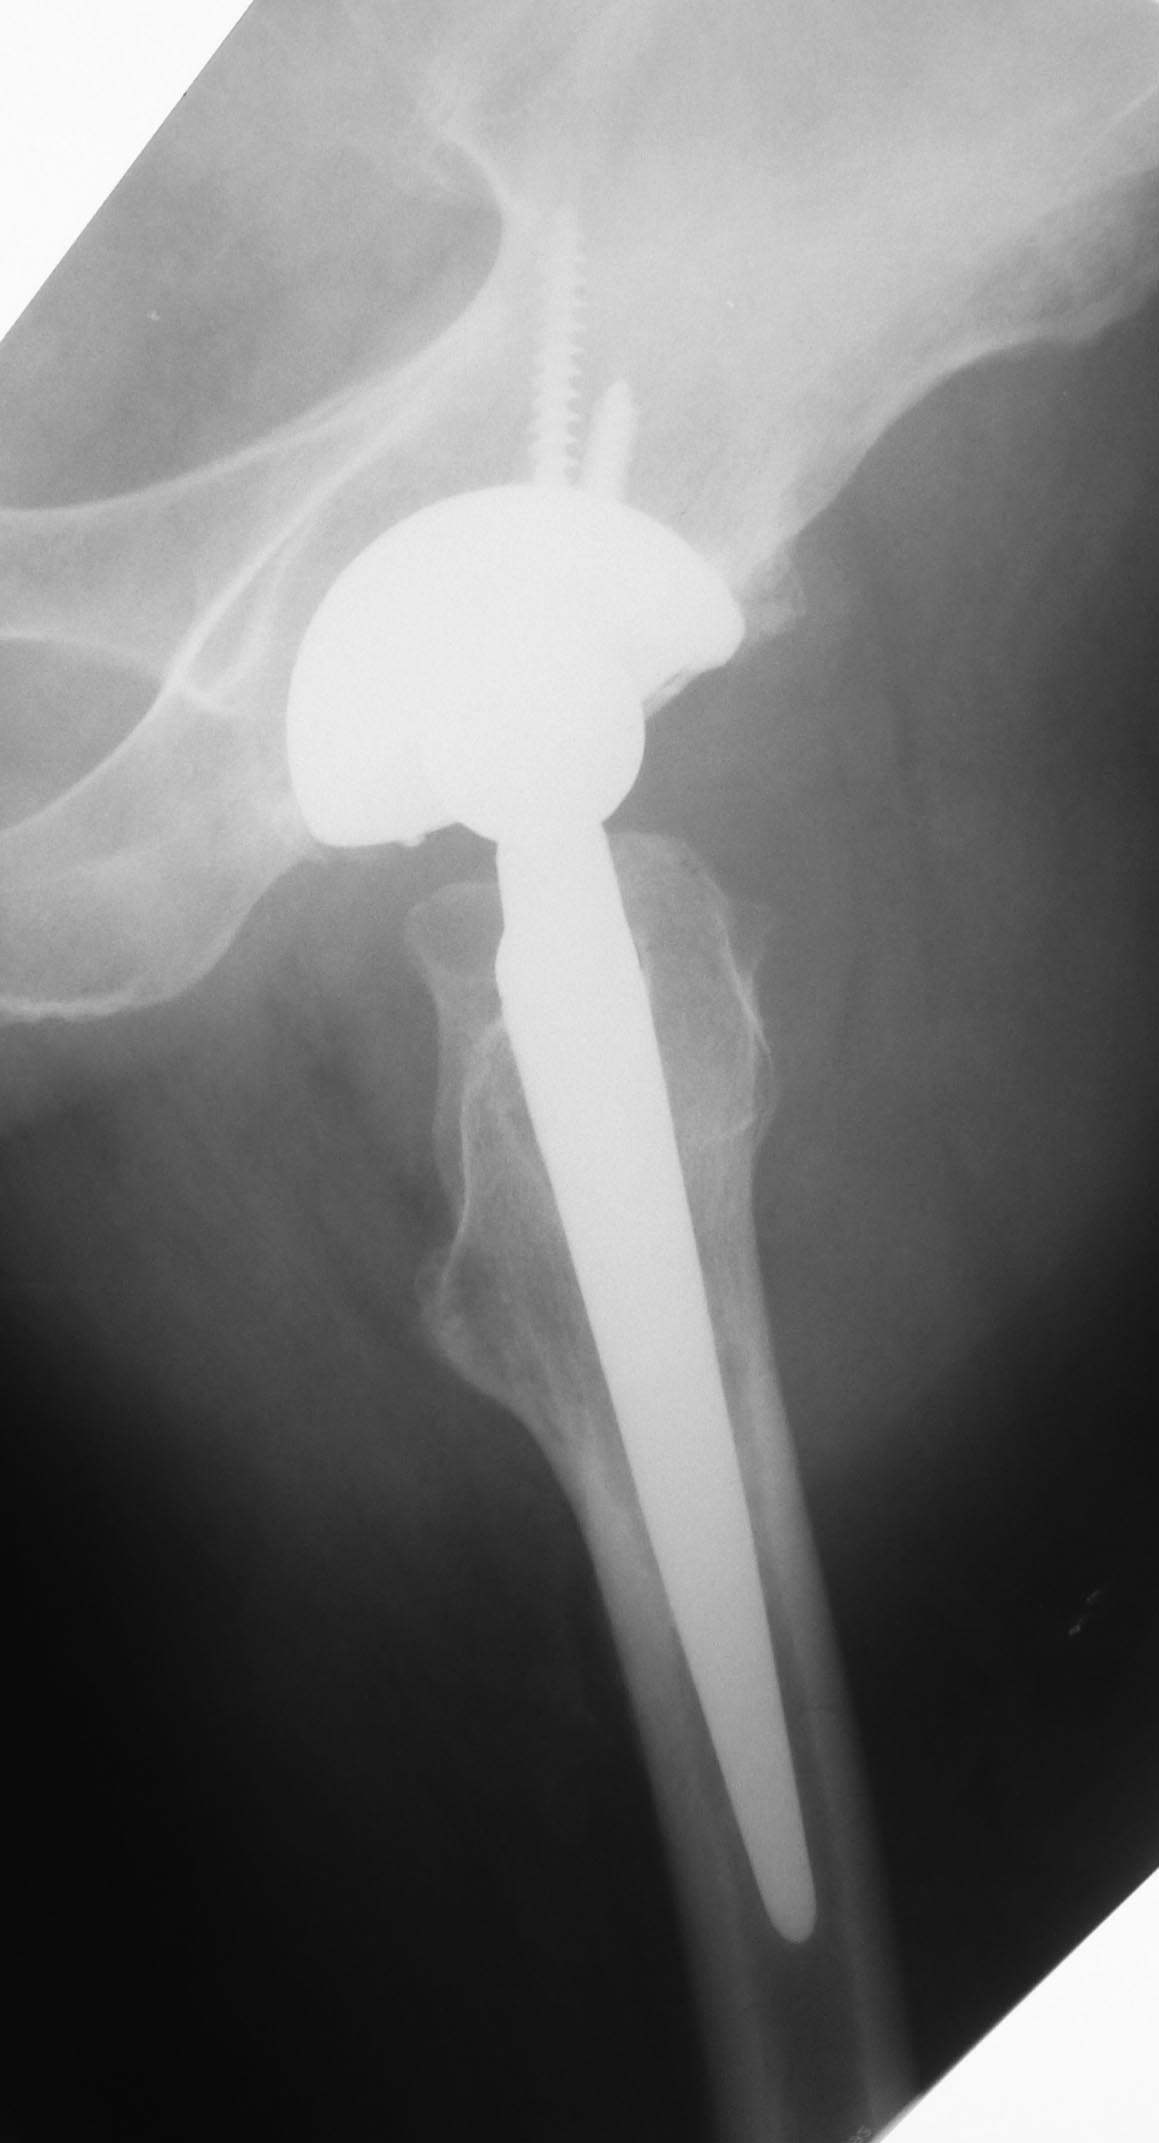

Пациент 55 лет. 6 лет после эндопротезирования по поводу коксартроза. На майские праздники упал со скамейки на ягодицу. За помощью обратился только через месяц из-за слегка болезненной припухлости в области ягодицы на стороне эндопротеза. При пункции под УЗ-контролем удалено около 200 мл гноеподобной жидкости из области эндопротеза (пункция выполнена через переднелатеральный доступ). Посев стерильный. Ни разу не отмечена лихорадка. СОЭ 87, С-рб 67. Жидкость снова набралась за неделю.

Может содержимым пунктата был дебрис? А вообще-то ревизия и без этого рано или поздно будет нужна - варусная позиция ножки с признаками шунтирования нагрузки.